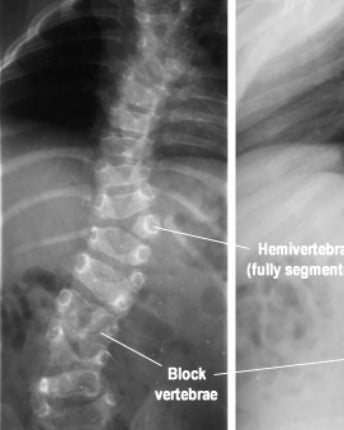

الجنف الخِلقي

ينتج الجنف الخِلقي عن تشوّهات في الفقرات تكون موجودة منذ الولادة، ويحدث نتيجة عدم اكتمال تطوّر العمود الفقري أثناء مرحلة النمو داخل الرحم.